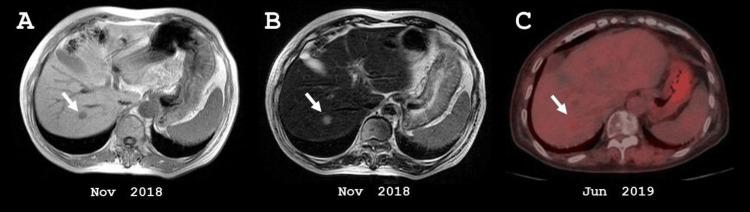

The prognosis of triple-negative breast cancer (TNBC) with hepatic metastasis is generally poor. Here, we report the case of a 70-year-old woman with TNBC whose hepatic metastasis did not recur for more than three years after radiofrequency ablation (RFA). During this period, the patient received chemotherapies with relatively mild side effects, such as eribulin mesylate and gemcitabine, maintaining a good quality of life. Although PARP inhibitors and immune checkpoint inhibitors are now available for TNBC, many cases are not eligible for these treatments due to the absence of specific target molecules. RFA may be a useful option in selected cases of hepatic metastasis from TNBC.

三阴性乳腺癌(TNBC)发生肝转移后的预后通常较差。在此,我们报告一例70岁的TNBC女性患者,其肝转移灶在接受射频消融(RFA)治疗后三年多未复发。在此期间,患者接受了副作用相对较轻的化疗,如甲磺酸艾瑞布林和吉西他滨,维持了良好的生活质量。尽管目前PARP抑制剂和免疫检查点抑制剂可用于TNBC治疗,但由于缺乏特定的靶分子,许多病例不符合这些治疗条件。对于TNBC肝转移的某些特定病例,RFA可能是一种有用的选择。